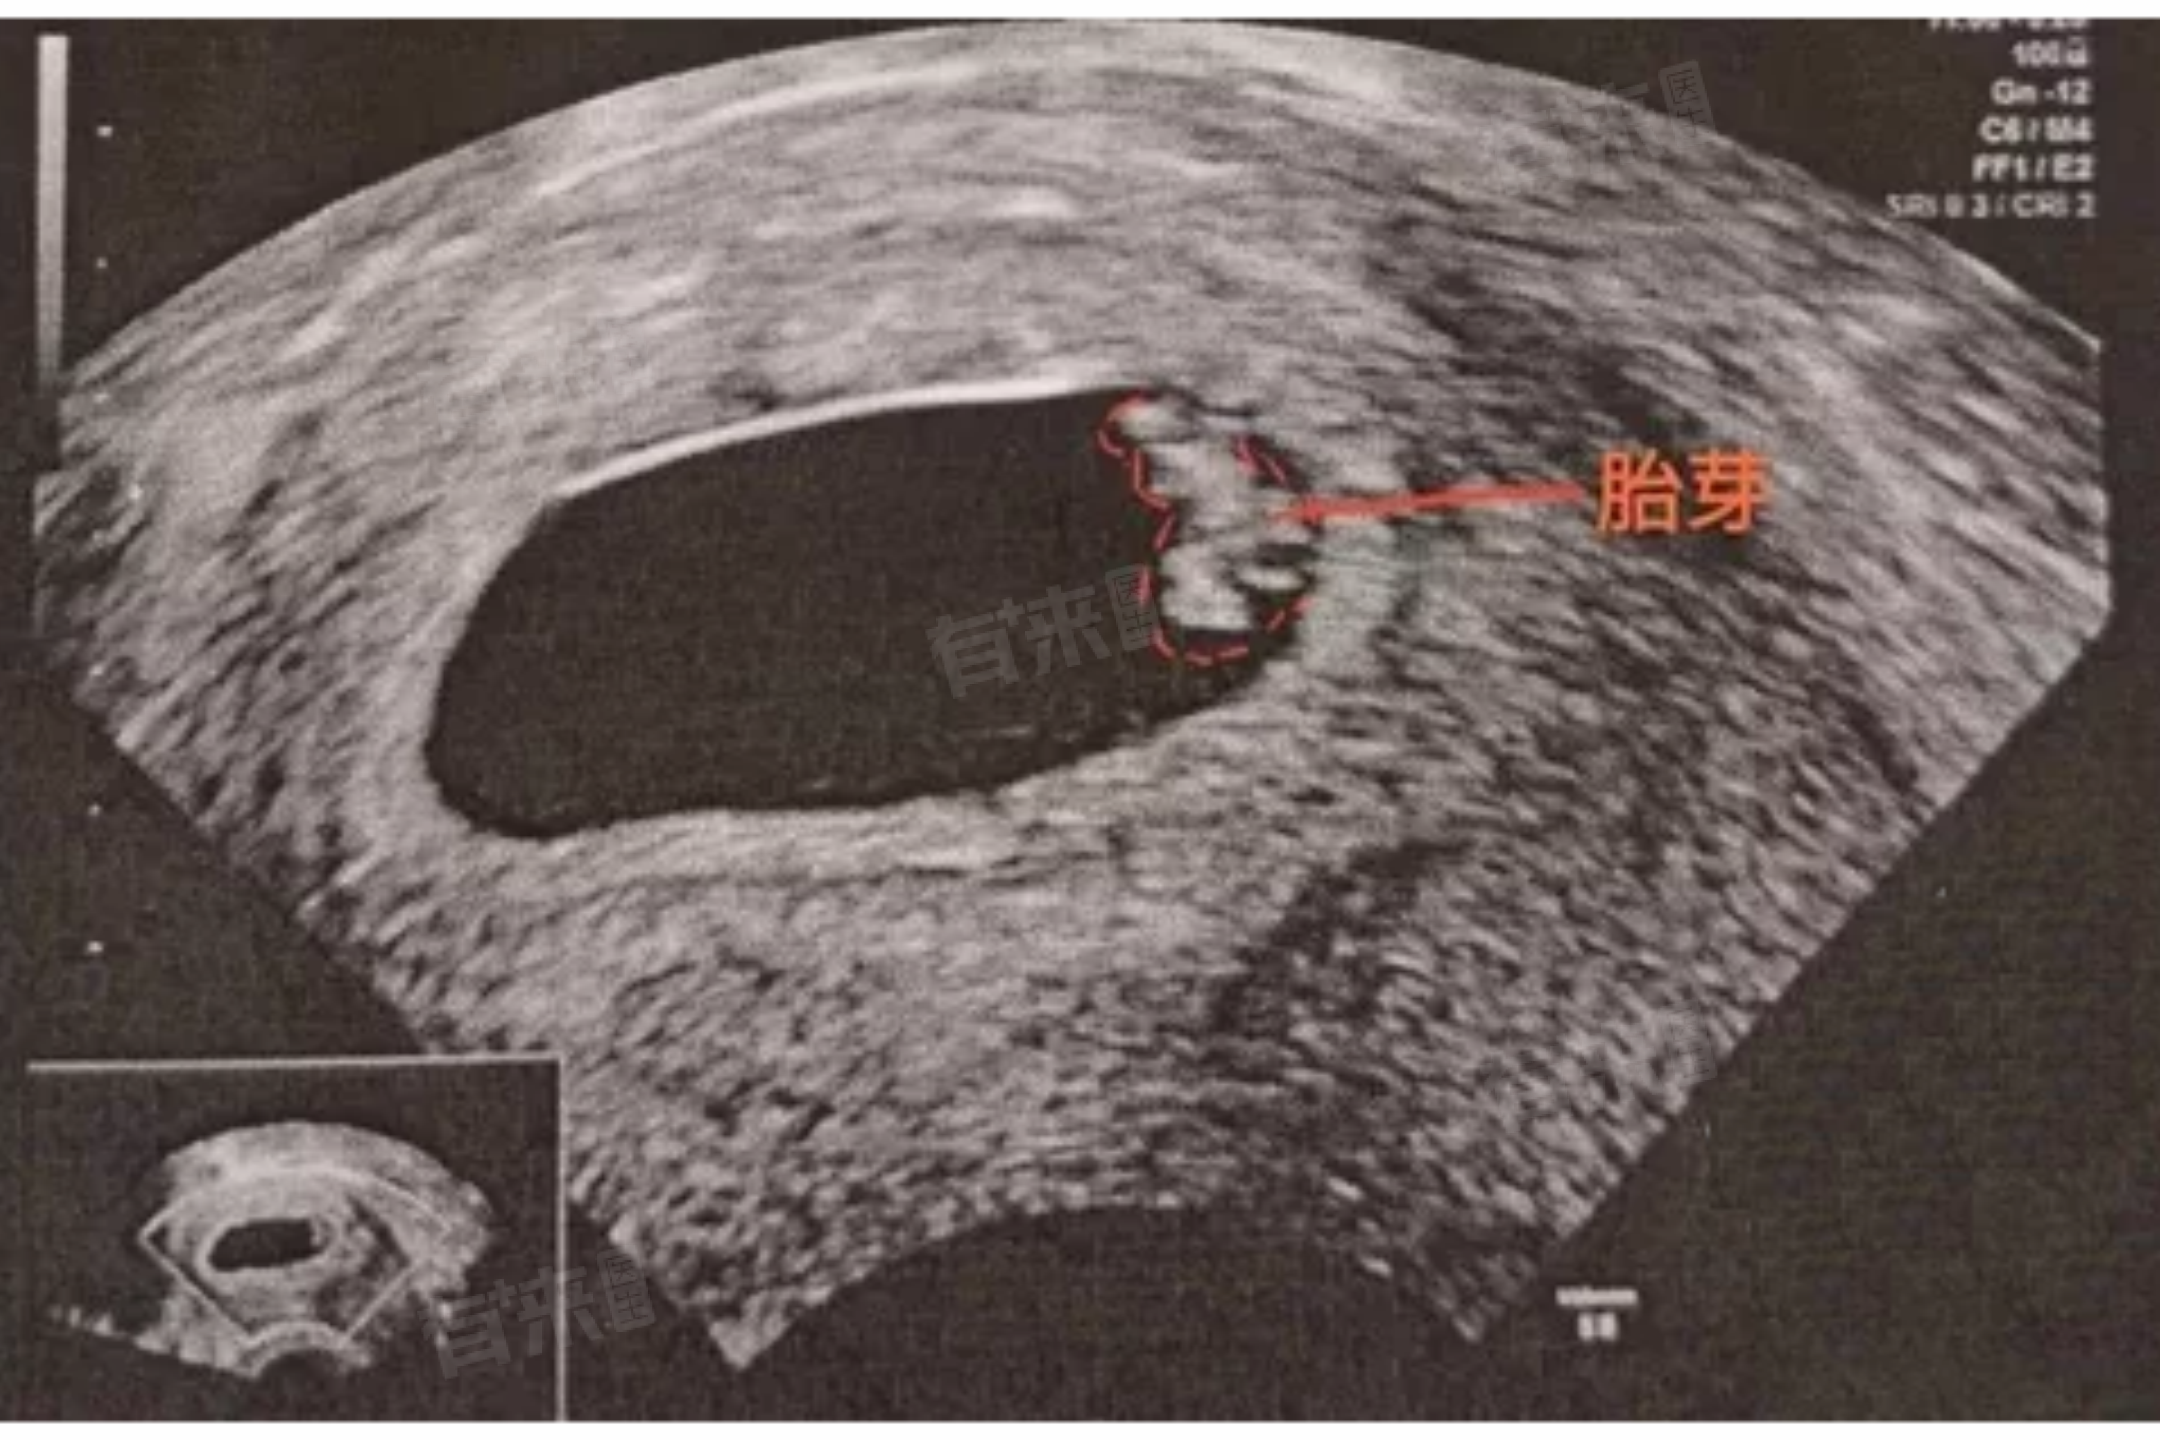

怀孕8周仍未检测到胎心胎芽,可能存在多种情况,有一些可能的补救措施,包括复查确认、改善生活方式等。